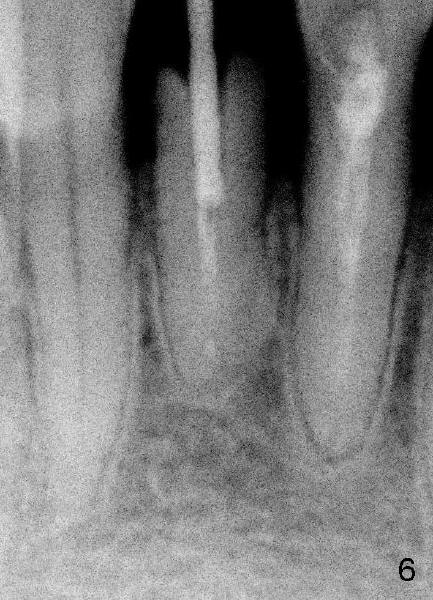

Fig.5 shows unfavorable crown/root ratio (9.41 mm vs. 5.74 mm); Fig.6 shows the longest post space that can be obtained using #2 Peeso bur. Return to main article